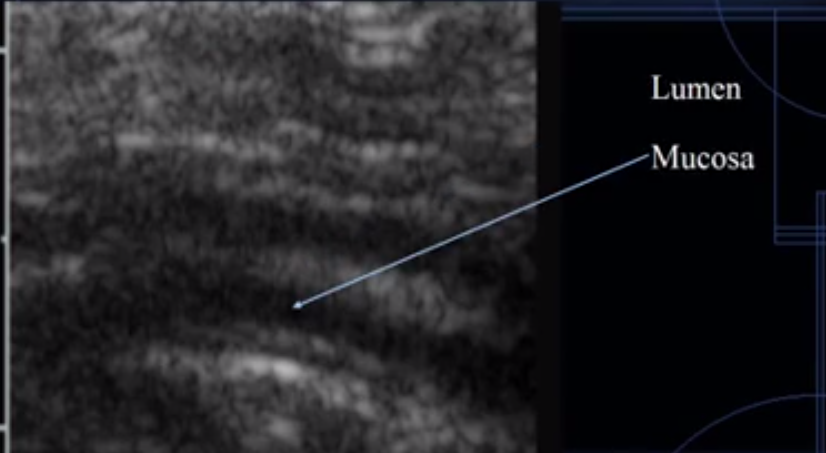

What does this image show?

Intestine

Which is the lumen?

Which is the mucosal layer?